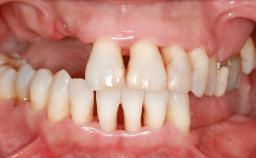

A 47-year-old Caucasian woman with a single-tooth edentulous space at the site of the left maxillary canine was referred for treatment. She had undergone traumatic extraction of this impacted canine several months before referral. Her chief complaint was the dissatisfying appearance of her smile. The patient desired a stable and esthetic rehabilitation of the site. Her dental history showed no evidence of periodontal disease or bruxism. She had no systemic diseases, was not taking any medications, and did not smoke. The extraoral examination revealed a high lip line and an inadequate soft-tissue volume at the defective canine site. Large black triangles were visible between the canine and its adjacent teeth.

Soft Tissue Anatomy Intact Defective

Bone Volume Horizontally and vertically sufficient Horizontally deficient Deficient vertically or deficient vertically AND horizontally